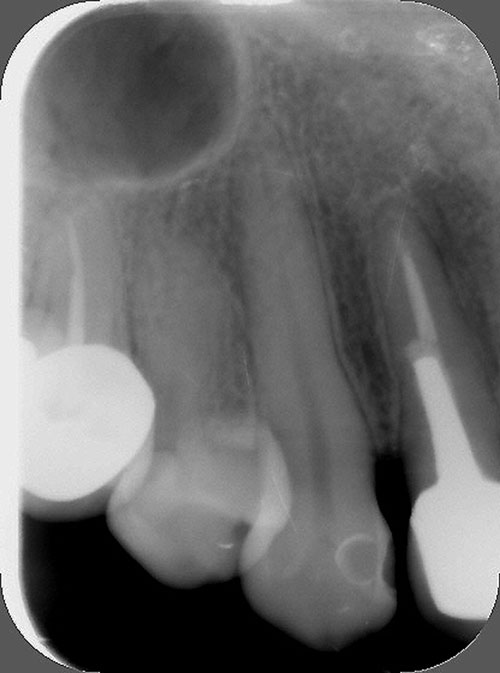

Observada la pieza clínica y radiograficamente, podemos ver una corona excesivamente sobredimensionada sobre un molar deficientemente endodonciado, que no solo muestra la pérdida ósea distal de la raíz en cuestión, sino también y producto de la mala endodoncia, un granuloma en la raíz mesial y en la furca.

Reabsorción Ósea Raíz Distal y en Furca/Endodoncia Defectuosa/Granuloma Raíz Mesial

Evidente Sobre Dimensionamiento Coronario

Endodoncias Defectuosas/ Mala Orientación de Perno Muñón

Reabsorción Ósea Raíz Distal y en Furca/Endodoncia Defectuosa/Granuloma Raíz Mesial

Amalgamas Desbordantes/Reabsorción Ósea Horizontal en 6-5 y Vertical en 6-7

Pérdida de un 33% de Inserción

Endodoncias Defectuosas/Carencia de Refuerzos Intradentarios/Coronas Sobre Dimensionadas/Reabsorción Ósea